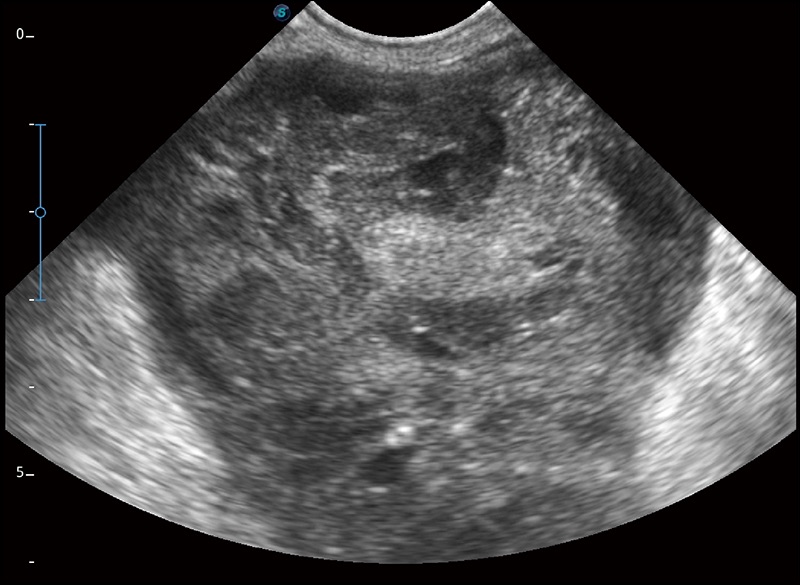

α1卓越的图像质量和便捷的工作流程,使每位宠物医生都能轻松扫查。其全面的兽用应用功能和紧凑型的结构设计,可以满足动物检查的多种需要。专业的预设检查模式和多领域测量软件包有助于为不同类型的动物提供检查, 让宠物医生能够出色的完成工作。

人机工程学设计

15.6英寸高清显示器

灵活可调节的显示器

防水面板设计

快速启动

静音系统